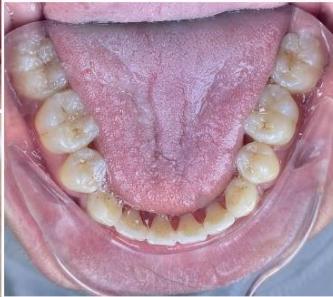

### b) Intraoral Examination

Intraoral examination revealed severe proclination and protrusion of both the maxillary and mandibular incisors [6]. The occlusal relationship was Class I at the canine (tooth 3) and first molar (tooth 6) levels bilaterally. A critical unfavorable biological factor was the proximity of the mandibular incisor roots to the labial cortical plate, representing a high-risk condition when planning extraction-based anterior retraction mechanics [10-12]. All four third molars were present.

Figure 2: Pre-Treatment Intraoral Photographs